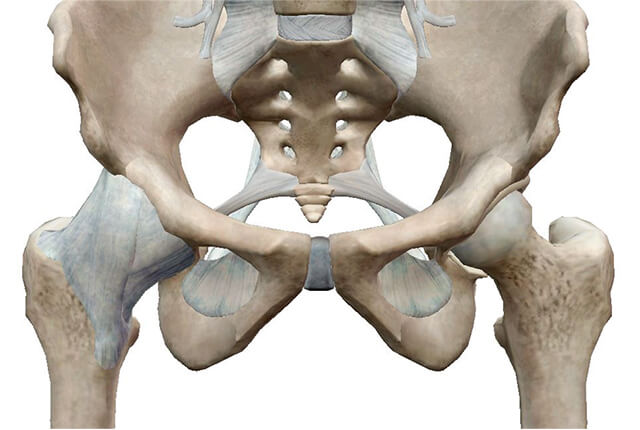

股関節の解剖と股関節痛図1

股関節は下肢の付け根に存在する球関節で広範な可動域を有する一方で、広口瓶の密封性高めているゴム(関節唇)のような構造物によって非常に安定した関節です(図1)。